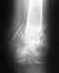

после операции на снимки было видно что кости сопоставлены неправильно, но врачи сказали что все срастется.

снимок сделан через месяц после операции